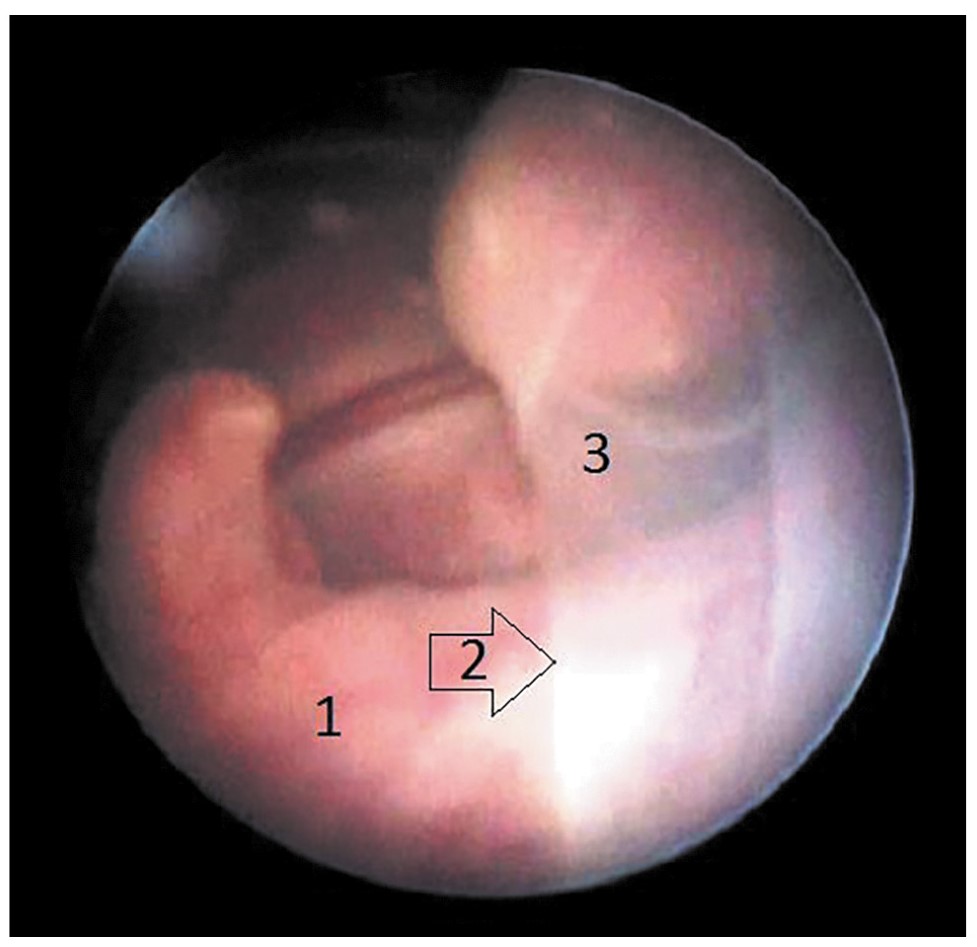

Непреднамеренная септостомия диагностировалась как во время фетоскопии по косвенным признакам, так и при проведении контрольного УЗИ через 15 мин после окончания операции и через 1 сут после ФЛКА и/или в родах после осмотра последа. Вынужденная септостомия (рис. 1) выполнялась торцом лазерного оптического волокна для проникновения в амнион донора с целью селективной коагуляции анастомозов, расположенных на «донорской» части плаценты далеко от амниотической перегородки.

Рис. 1. Вынужденная септостомия.

Примечание: 1 – переднее расположение плаценты; 2 – троакар/интродюсер; 3 – амниотическая перегородка.

Note: 1 – anterior location of the placenta; 2 – trocar/introducer; 3 – intertwin membrane.